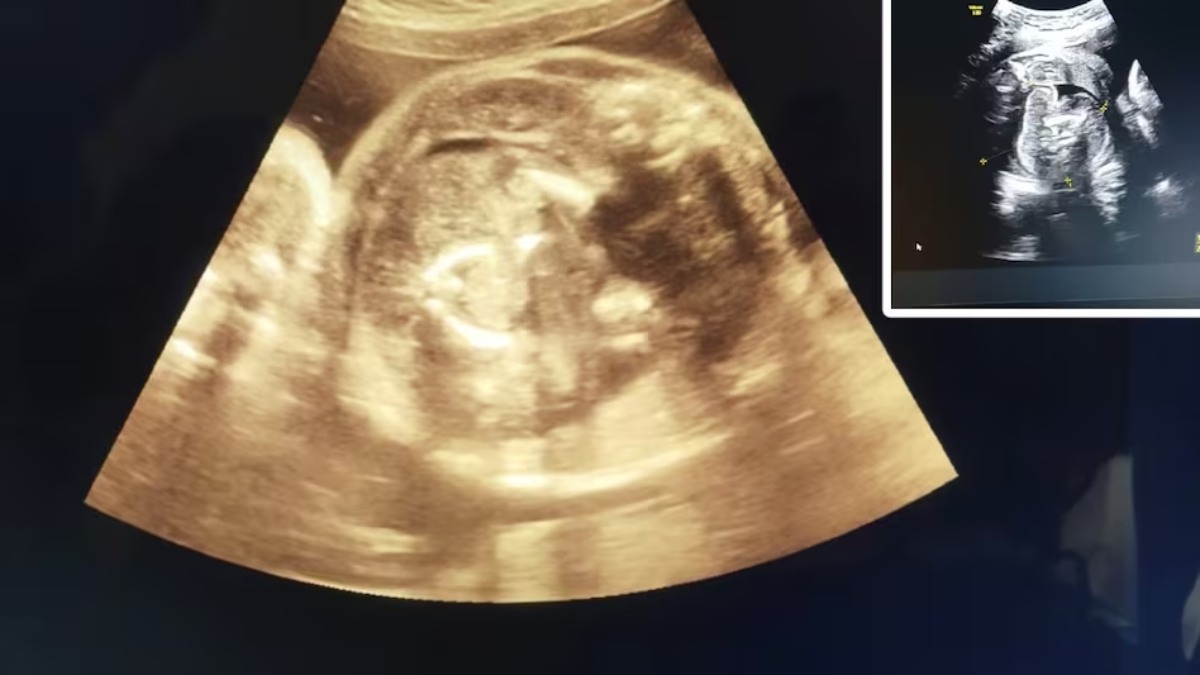

Fetus in Feto: महाराष्ट्र (Maharashtra) के बुलढाना (Buldhana) जिले से हैरान करने वाला मामला सामने आया है। यहां एक गर्भवती महिला की सोनोग्राफी (Sonography of a pregnant woman) चर्चा में है। डॉक्टर ने महिला की सोनोग्राफी का बारीकी से अध्यन किया तो महिला के पेट में बच्चा और बच्चे के पेट में एक और बच्चा दिखा। इसके बाद डॉक्टर चौंक गए। डॉक्टरों ने अपने संदेह को दूर करने के लिए महिला की तीन बार सोनोग्राफी की। सभी सोनोग्राफी में महिला के पेट में भ्रूण और उस भ्रूण के पेट में एक और भ्रूण दिखा। महिला को डिलीवरी में कोई समस्या न हो, इसलिए उसे बड़े अस्पताल भेज दिया।

सोनोग्राफी करते समय उन्हें महिला के पेट में बच्चा तो दिखाई दिया। साथ ही उसी बच्चे के पेट कुछ और भी दिखाई दिया। डॉक्टर अग्रवाल ने और तीन बार महिला की सोनोग्राफी की तो उन्हें दिखाई दिया कि जो पेट में बच्चा है, उसके पेट में भी एक बच्चा है। डॉक्टर अग्रवाल ने यह बात अपने वरिष्ठों को बताई. वरिष्ठों ने गर्भवती महिला को डिलीवरी और किसी भी प्रकार की कोई समस्या न हो, इसलिए संभाजीनगर भेज दिया।

महिला रोग विशेषज्ञ (Gynecologist) डॉक्टर प्रसाद अग्रवाल ने कहा फिलहाल भ्रूण से महिला को तो कोई प्रॉब्लम नहीं है। हालांकि डिलीवरी के बाद जन्मे बच्चे का जल्द उपचार नहीं हुआ तो उसकी ग्रोथ में बाधा आ सकती है।

वहीं सिविल सर्जन डॉक्टर भागवत भुसारी ने बताया कि इसे डॉक्टरी भाषा में fetus in feto (भ्रूण में भ्रूण) कहा जाता है। दुनिया में ऐसे मामले 200 के लगभग हुए हैं, जिसमें भारत में ऐसे मामले अबतक 15 से 20 हुए हैं।